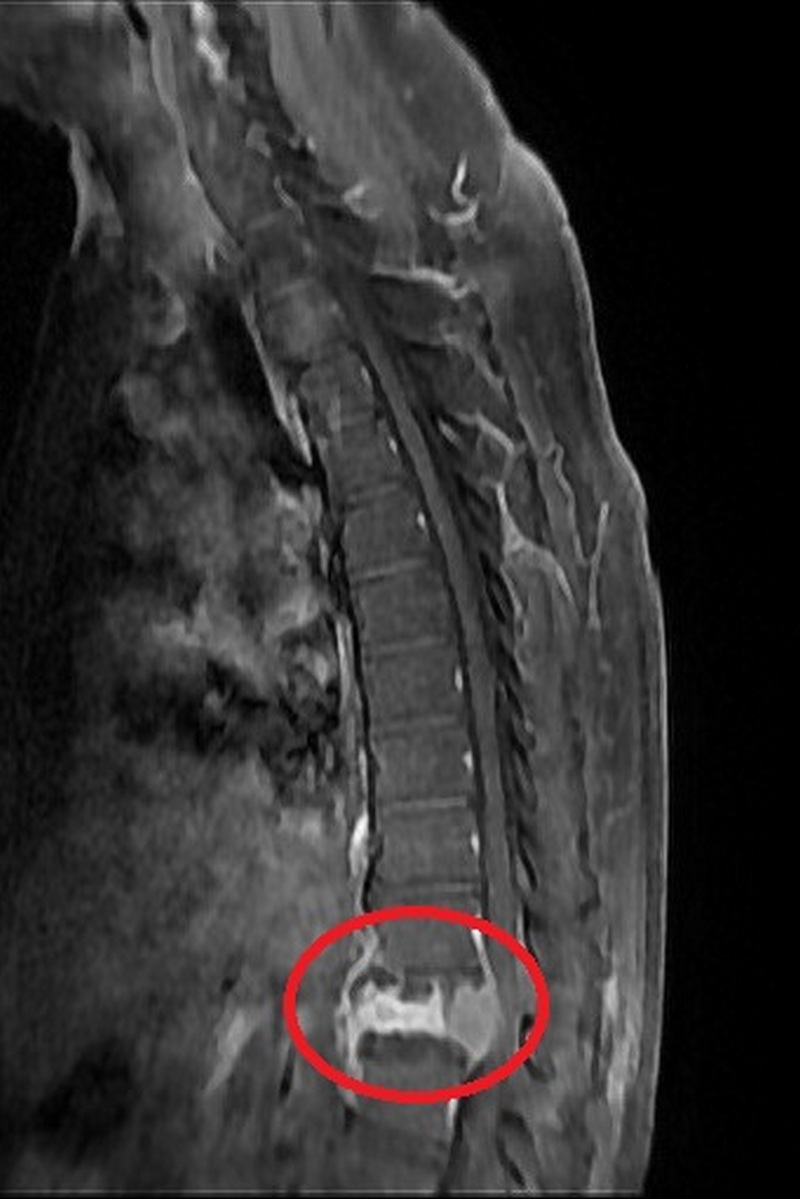

透過X光、核磁共振檢查,發現邱先生胸椎第12節有塌陷情形,且已經壓迫神經管,影像懷疑為腫瘤骨轉移導致的非單純骨質疏鬆之壓迫性骨折,進一步抽血檢查更顯示腫瘤標記數值增高。經醫師進行「減壓及微創釘手術」,解除壓迫危機,術後隔天邱先生已能下床行走,並在傷口穩定後由腫瘤科團隊接手治療。

神經管受壓迫須進行良好的減壓,才可以讓神經學症狀達到改善,以邱先生為例,醫師在術中除給予良好的減壓外,還進行微創釘固定,幫助穩定脊椎。

「減壓及微創釘手術」首先需要將脊椎後側的椎板切除進行完整減壓後移除部分腫瘤,並透過術中X光檢查確認位置,將4根微創骨釘分別固定在胸椎第11節及腰椎第1節,最後再以金屬桿連接兩端,不需破壞很多肌肉層即可達到穩定脊椎的作用。